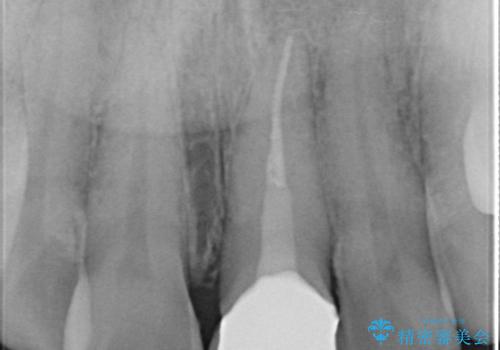

前歯が黒くなってきた。オールセラミッククラウン

- 前歯の変色を主訴に来院されました。

根管治療は希望されなかったので、リスクを説明した上でオールセラミッククラウンの治療を行っています。